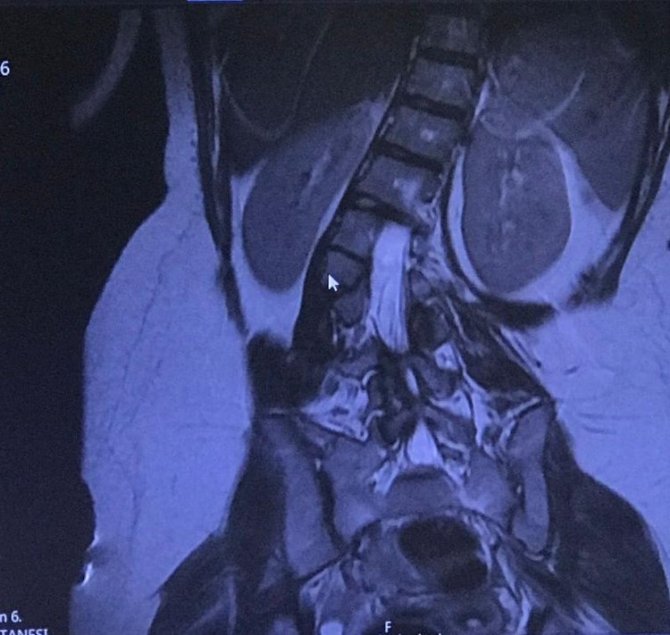

Eda'nın omurgasındaki eğriliğinden doğuştan kaynaklandığını anlatan Medicana International İzmir Hastanesi'nde görevli Ortopedi ve Travmatoloji Uzmanı Doç. Dr. Mutlu Çobanoğlu, "Doğuştan kaynaklanan skolyoz, genellikle ilerleyici tipte oluyor. Çocuk büyüdükçe kendini göstermeye başlıyor. Dışarıdan bakılınca gözükmeyebiliyor. Eda'daki gelişim kusuru omurgasını belli bir tarafa doğru itmişti. Duruşunda dengesizlik meydana geliyordu. Yaşı daha küçükken ağrısı muhtemelen olmuyordu ancak büyüdükçe ağrıları olmaya başladı. Hastadaki skolyozun derecesi ve hastada meydana getirdiği şekil bozukluğuna göre tedavi seçenekleri var. Her skolyoz mutlaka ameliyat olmalı diye bir durum söz konusu değil" diye konuştu. Doç. Dr. Çobanoğlu, skolyozun tedavi edilmediği durumlarda, kişinin solunum problemleri yaşayabildiğini, omurgada dengeli bir yük dağılımı olmadığı için artan ağrılara bağlı olarak kireçlenme olabileceğini ve tüm omurganın bu durumdan etkilenebileceğini de sözlerine ekledi.